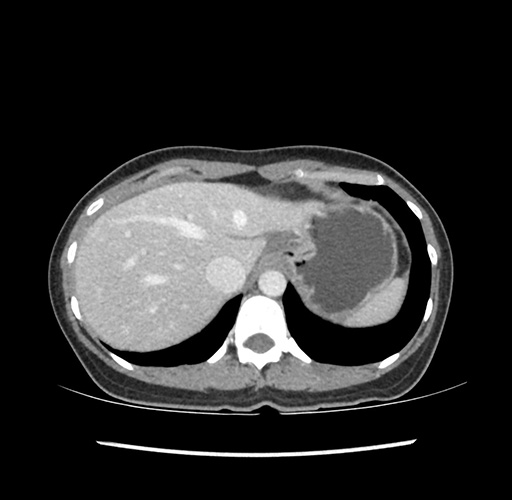

Left lateral sectionectomy [case 12]

Imaging Analysis

Look through the patient's CT scan to identify any areas of concern for the necessary procedure.

Based on your CT findings, which issue(s) would give reason for "planned slowing down moment(s)" in this case?

Considering a standard left lateral sectionectomy procedure, what step(s) of the operation would you do differently in this case ?